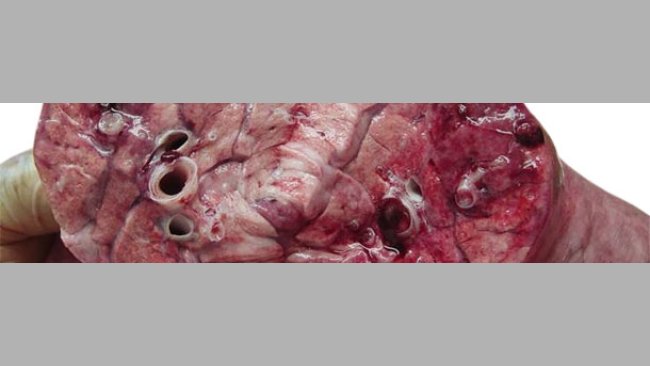

Caso clínico: Pneumonia necrótica em leitões lactantes

Numa exploração de multiplicação situada no México observa-se um aumento da mortalidade na maternidade coincidindo com um aumento da temperatura e humidade ambientais.